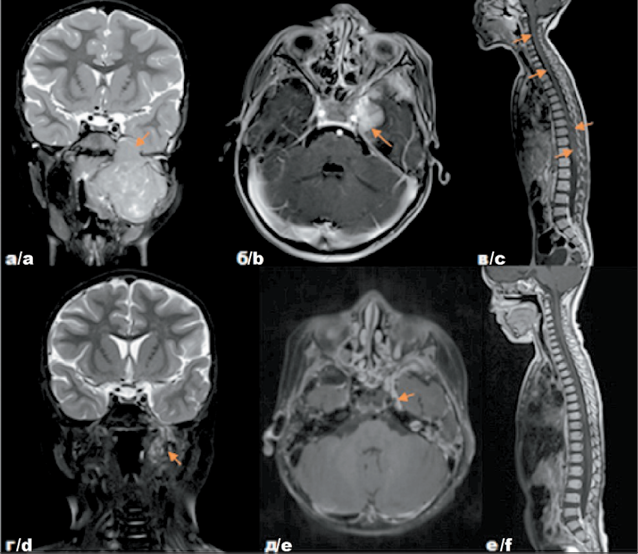

4. Рис. 4. Собственные результаты исследований пациентки П. с диагнозом: Эмбриональная рабдомиосаркома параменингеальной локализации с интракраниальным распространением, метастатическое поражение лимфатических узлов, лептоменингеальные метастазы в спинном мозге, стадия IV (T2вN1M1. IRS IVa) до лечения – на томограммах во фронтальной (а), аксиальной (б) и сагиттальной (в) проекциях и после комбинированного лечения – на томограммах во фронтальной (г), аксиальной (д) и сагиттальной (е) проекциях. Примечание: рисунок выполнен авторами